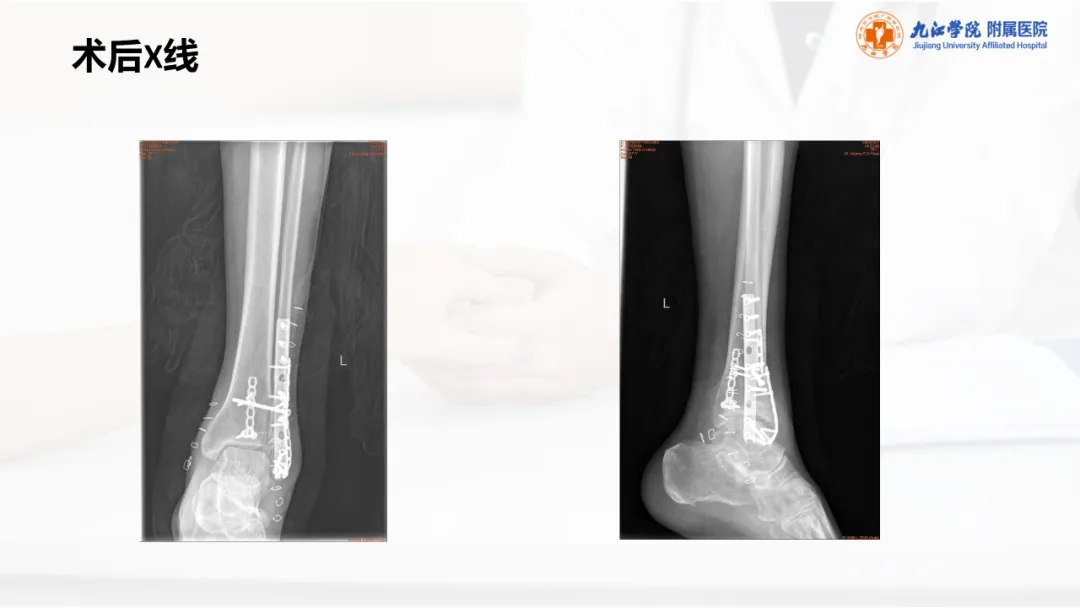

当前位置:首页>PPT>PPT纯享:陈旧性踝关节骨折的治疗案例(内附文献推荐)

PPT纯享:陈旧性踝关节骨折的治疗案例(内附文献推荐)